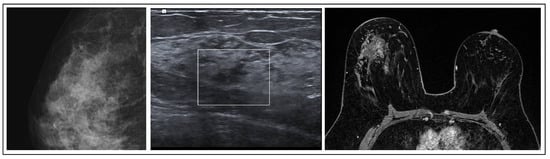

FEA is commonly found alongside other suspicious lesions and exhibits imaging characteristics similar to both malignant and benign lesions. When observed on mammography, it manifests as clustered calcifications, while on ultrasound, it may manifest as an irregular hypoechoic mass. In MRI scans, FEA might be concealed or manifest as either a mass or a non-mass area exhibiting nonspecific characteristics [27] (Figure 4). FEA is histologically categorized within the spectrum of columnar cell lesions in the breast. This spectrum includes columnar cell alteration and hyperplasia, both of which lack atypia; however, the presence of atypia is what classifies it specifically as FEA [28].

Figure 4. FEA radiological features.